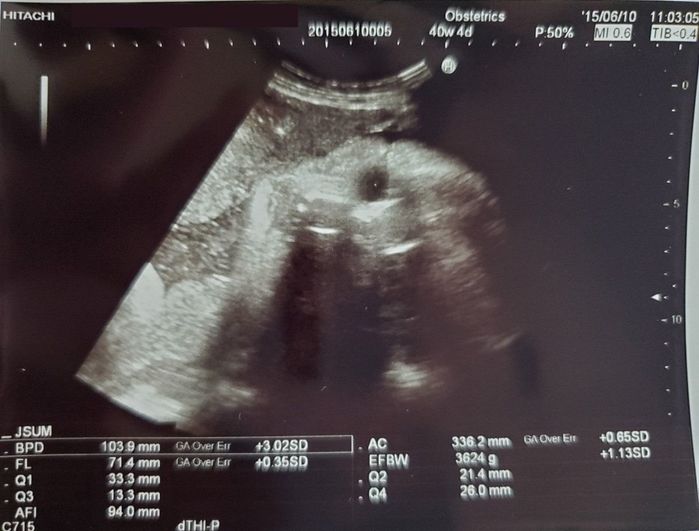

妊娠40週目のエコー写真 - もうすぐ会えるね!

出産前最後のエコー。最後までこちらをじっと見ている赤ちゃん。このころ、出産をうながすために散歩や外出をしていたのですが、娘はおなかのなかでのんびりとくつろいでいるよう。出てくる気配がありませんでした。先生と相談し、5日後に陣痛促進剤を使って出産する事が決まりました。

出産当日、1回目の陣痛促進剤を入れた直後におなかが痛くなってしまったため、急きょ緊急帝王切開となりました。娘は41週2日で生まれ、身長51.0cm、体重はおおきめの3662gでした。